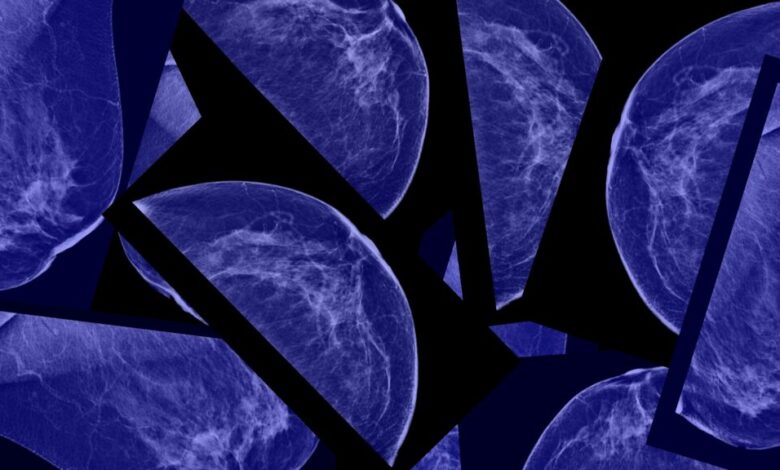

The use of AI in mammograms is also a growing area of interest. AI tools are being developed to predict not only current cancerous cells but also future risks of breast cancer and cardiovascular disease. The FDA recently authorized an algorithm that can predict a patient’s risk of developing breast cancer in the next five years, showcasing the potential of AI in preventive healthcare.